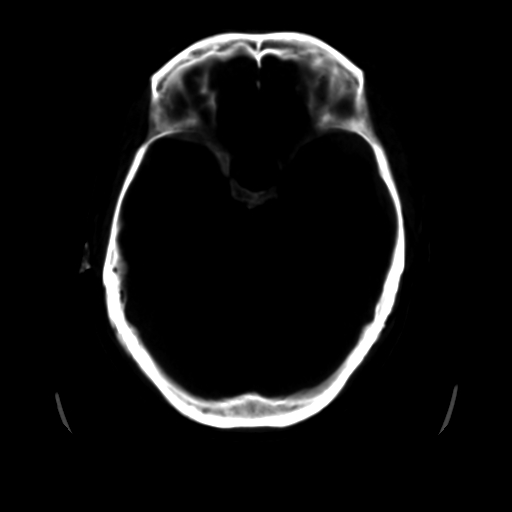

男,51岁,头外伤一小时,呕吐两次。

1)左侧中颅窝蝶骨翼后方硬膜外血肿。2)左侧颞顶部硬膜下血肿。3)蛛网膜下腔出血。4)左侧筛窦及双侧蝶窦炎症(或积血)。5)左侧额部头皮软组织肿胀。